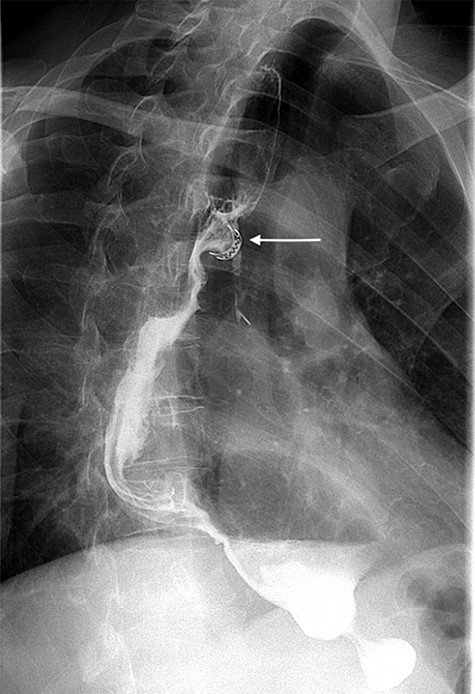

After this endoscopic procedure, the patient was subjected to barium swallow examination that demonstrated the OTSC on the gastric conduit and no filling of the left bronchus (Figure 3), following by complete resolution of symptoms. At the follow-up time of 6 months, the patient is asymptomatic and there is no recurrence of the fistula. To the best of our knowledge, this is the first reported case of GBF treated with OTSC in the literature.

Postoperative barium swallow demonstrating the OTSC on the gastric conduit (white arrow) and no filling of the left bronchus.